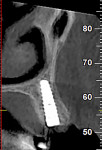

A 97½-year-old patient presented with a hopeless tooth No. 12 and was deemed a less-than-ideal candidate for immediate provisionalization. The tooth, which was fractured to the gingival margin, was extracted atraumatically25 with the use of piezosurgery (Mectron, dental.mectron.us) to minimize trauma to the bone and gingiva and decrease disruption of the blood supply (Figure 10). After placement of a dental implant in the palatal portion of the socket (Figure 11), the gap was grafted with partially demineralized ground dentin (KometaBio). The graft was fabricated into an L-PRF block and covered with an amnion-chorion barrier (BioXclude®, Snoasis Medical, snoasismedical.com), which has been shown to be anti-infective and contain growth factors and can be left in an exposed manner.48-50 A CBCT taken at the time of uncovering showed excellent bone-to-implant contact visually, alveolar width preservation, and graft consolidation with a radio-opacity identical to that of the surrounding bone (Figure 12). The soft-tissue profile 1 year after the implant was prosthetically loaded is shown in Figure 13. Presently, the patient is 102½ years old, and 5 years post-surgery the restoration looks the same or better.